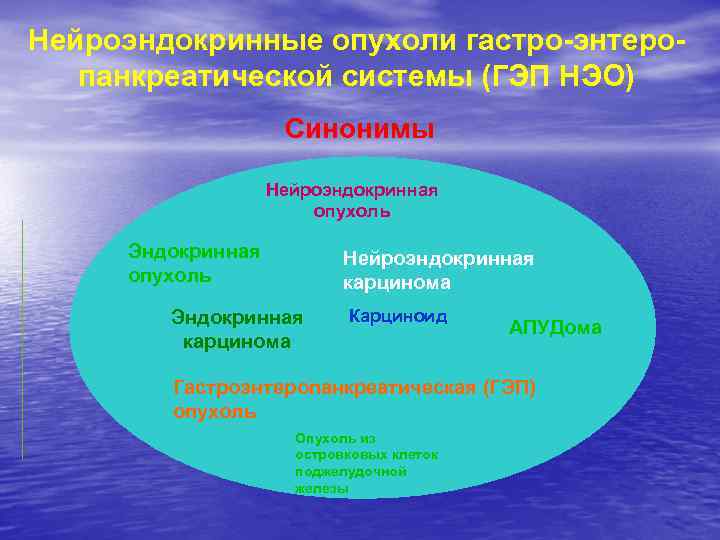

Нейроэндокринные опухоли гастро-энтеропанкреатической системы (ГЭП НЭО) Синонимы Нейроэндокринная опухоль Эндокринная опухоль Нейроэндокринная карцинома Эндокринная карцинома Карциноид АПУДома Гастроэнтеропанкреатическая (ГЭП) опухоль Опухоль из островковых клеток поджелудочной железы